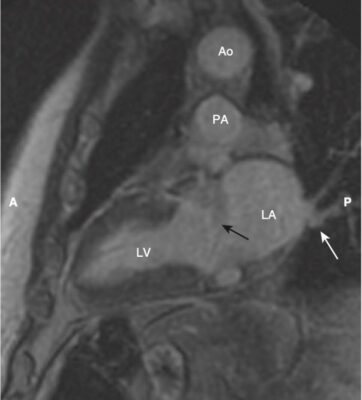

- Một trong những lợi ích của MRI là hình ảnh của nó có thể được hiển thị ở bất kỳ mặt phẳng nào. Bên cạnh các mặt phẳng cắt ngang (axial), đứng dọc (sagittal) và đứng bên (coronal, trán), có một số góc nhìn đặc hiệu thường được sử dụng trong MRI tim cho phép hình dung rõ nhất về tim. Chúng được gọi là trục dài cắt ngang (còn được gọi là mặt cắt bốn buồng), trục dài thẳng đứng, trục ngắn và mặt cắt ba buồng.

- Cấu trúc giải phẫu của tim trong các mặt phẳng cắt ngang, đứng dọc và trán giống như được thấy trên CT (Hình 16).

- Mặt cắt trục dài cắt ngang (bốn buồng) giống hình cắt ngang và được sử dụng tốt nhất để đánh giá vách ngăn và thành bên và đỉnh của tâm thất trái, thành tự do của tâm thất phải và kích thước của các buồng tim. Các van hai lá và van ba lá đặc biệt nhìn rõ ràng trong hình ảnh này (Hình 17).

- Trục dài đứng dọc giống như lát cắt đứng dọc và được sử dụng để đánh giá thành trước và thành dưới và đỉnh của tâm thất trái (Hình 18).

- Lát cắt ba buồng tương tự như lát cắt đứng bên và hiển thị gốc động mạch chủ và van động mạch chủ, đường ra thất trái, van hai lá, các thành trước vách và thành dưới bên của tâm thất trái (Hình 20).